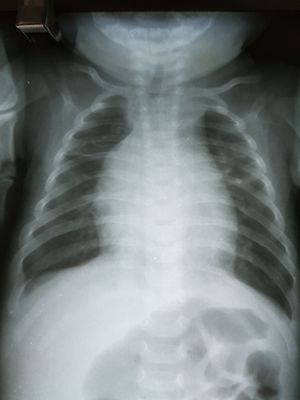

Cardiomegalia